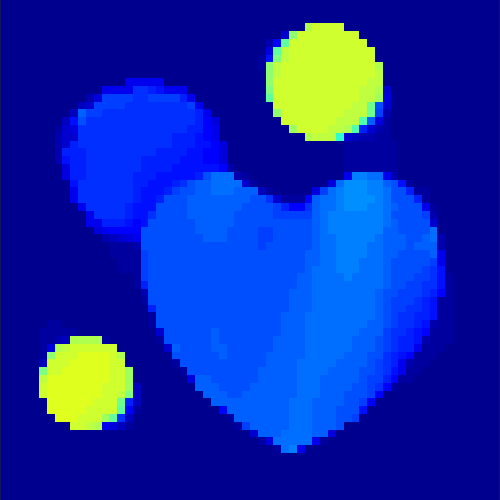

The first data set consists of a heart-shaped region and three circles on a static background (see figure 1 (a)). The two smaller circles are assumed to belong to

the same tissue type and therefore to the same subregion, which causes a total of four subregions, including the background. To simulate a more realistic application of dynamic SPECT

imaging, we used a synthesized representation of a rat liver as a second data set (see figure 1 (b)). The temporal concentration curves used to simulate the data sets

are shown in figure 2. As before, the total number of subregions was chosen to be equal to four in order to provide a both simple and realistic shape model.

As one can see in both figures, the reconstruction method applied to each data set performs very well, especially in contrast to the simple alternating EM method. This clearly shows the benefits of the proposed regularization methods. In case of noise-free given data, the shape of every object, where especially the heart is of higher interest, is clearly defined. As expected, we often observe errors in the edges of each region and where two regions are directly connected (the heart and the upper left circle). This causes the algorithm to incorrectly assign these pixels to another region. Furthermore, the reconstruction difficulties increase with an increase in noise. Some more pixels are assigned to the wrong region, which leads to a small hole-like structure within the heart region and causes a slight blurring effect. In the second data set the method clearly outperforms several other approaches by providing very clearly defined regions and even reconstructing fine structures of the phantom. However, as mentioned before, a clear reconstruction of the rat liver required highly optimized parameter sets, which makes the whole problem quite susceptible to parameter changes.